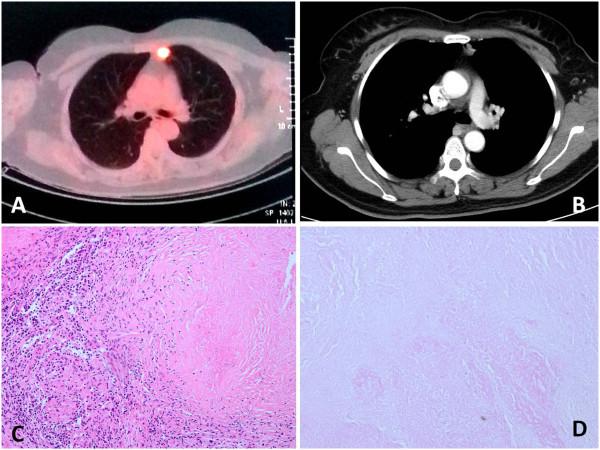

Motor neuron disease (MND) is occasionally aggravated by chronic infection. A misdiagnosed case of tuberculosis with MND is illustrated in a 45-year-old woman who underwent successful VATS wedge excision, which is presented herein. MND in an adult is a rare clinical entity. In order to facilitate the preoperative diagnosis and avoid the misdiagnosis of this disease, more etiological factors need to be considered.

运动神经元病(MND)偶尔会因慢性感染而加重。本文介绍了一名45岁女性,她患有MND却被误诊为肺结核,最终成功接受了电视辅助胸腔镜手术(VATS)楔形切除术。成人MND是一种罕见的临床病症。为便于术前诊断并避免该病的误诊,需要考虑更多的病因因素。